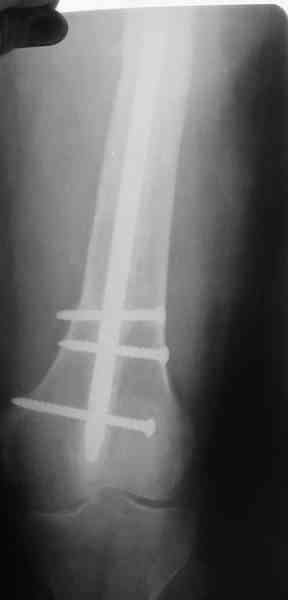

4, 5, 6 - рентгенограммы бедра и фотографии пациентки (прошу прощения за низкое качество рентгеновских снимков) от 7 сентября 2007 г.

В качестве демонстрации лечения канального остеомиелита бедренной кости представляем пациентку (см. parts 2 и 3), которая как раз сегодня была у нас на контрольном осмотре. В мае этого года мы произвели ей фиксацию бедренной кости штифтом-спейсером по поводу ложного сустава и канального остеомиелита бедренной кости. Через 4 недели после операции свищи закрылись. Сейчас она ходит с полной нагрузкой на конечность.